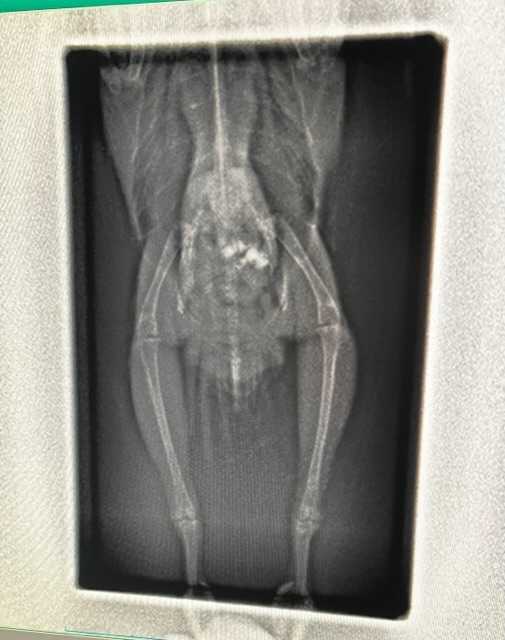

こんばんは

昨日、小夏(インコ)の調子が悪いと書きましたが

高いところから着地した時にどうやら脚を痛めてしまったみたい。

結局病院に連れていきました

この後、小夏のレントゲン写真うつります。

無理な方はここで読むのを控えてください。

ちなみに小夏は投薬で治るそうなのでご心配なく。

正直、見てもよくわからなかったのですが

小夏は骨にも異常無くほかの臓器にも異常がみられなかったので

このまま痛み止めと抗生剤で治っていくとのことでした。

今回いろいろ診てもらったので12760円也

たっか~~~~~~~い💦

保険利かないからしょうがないですよね。